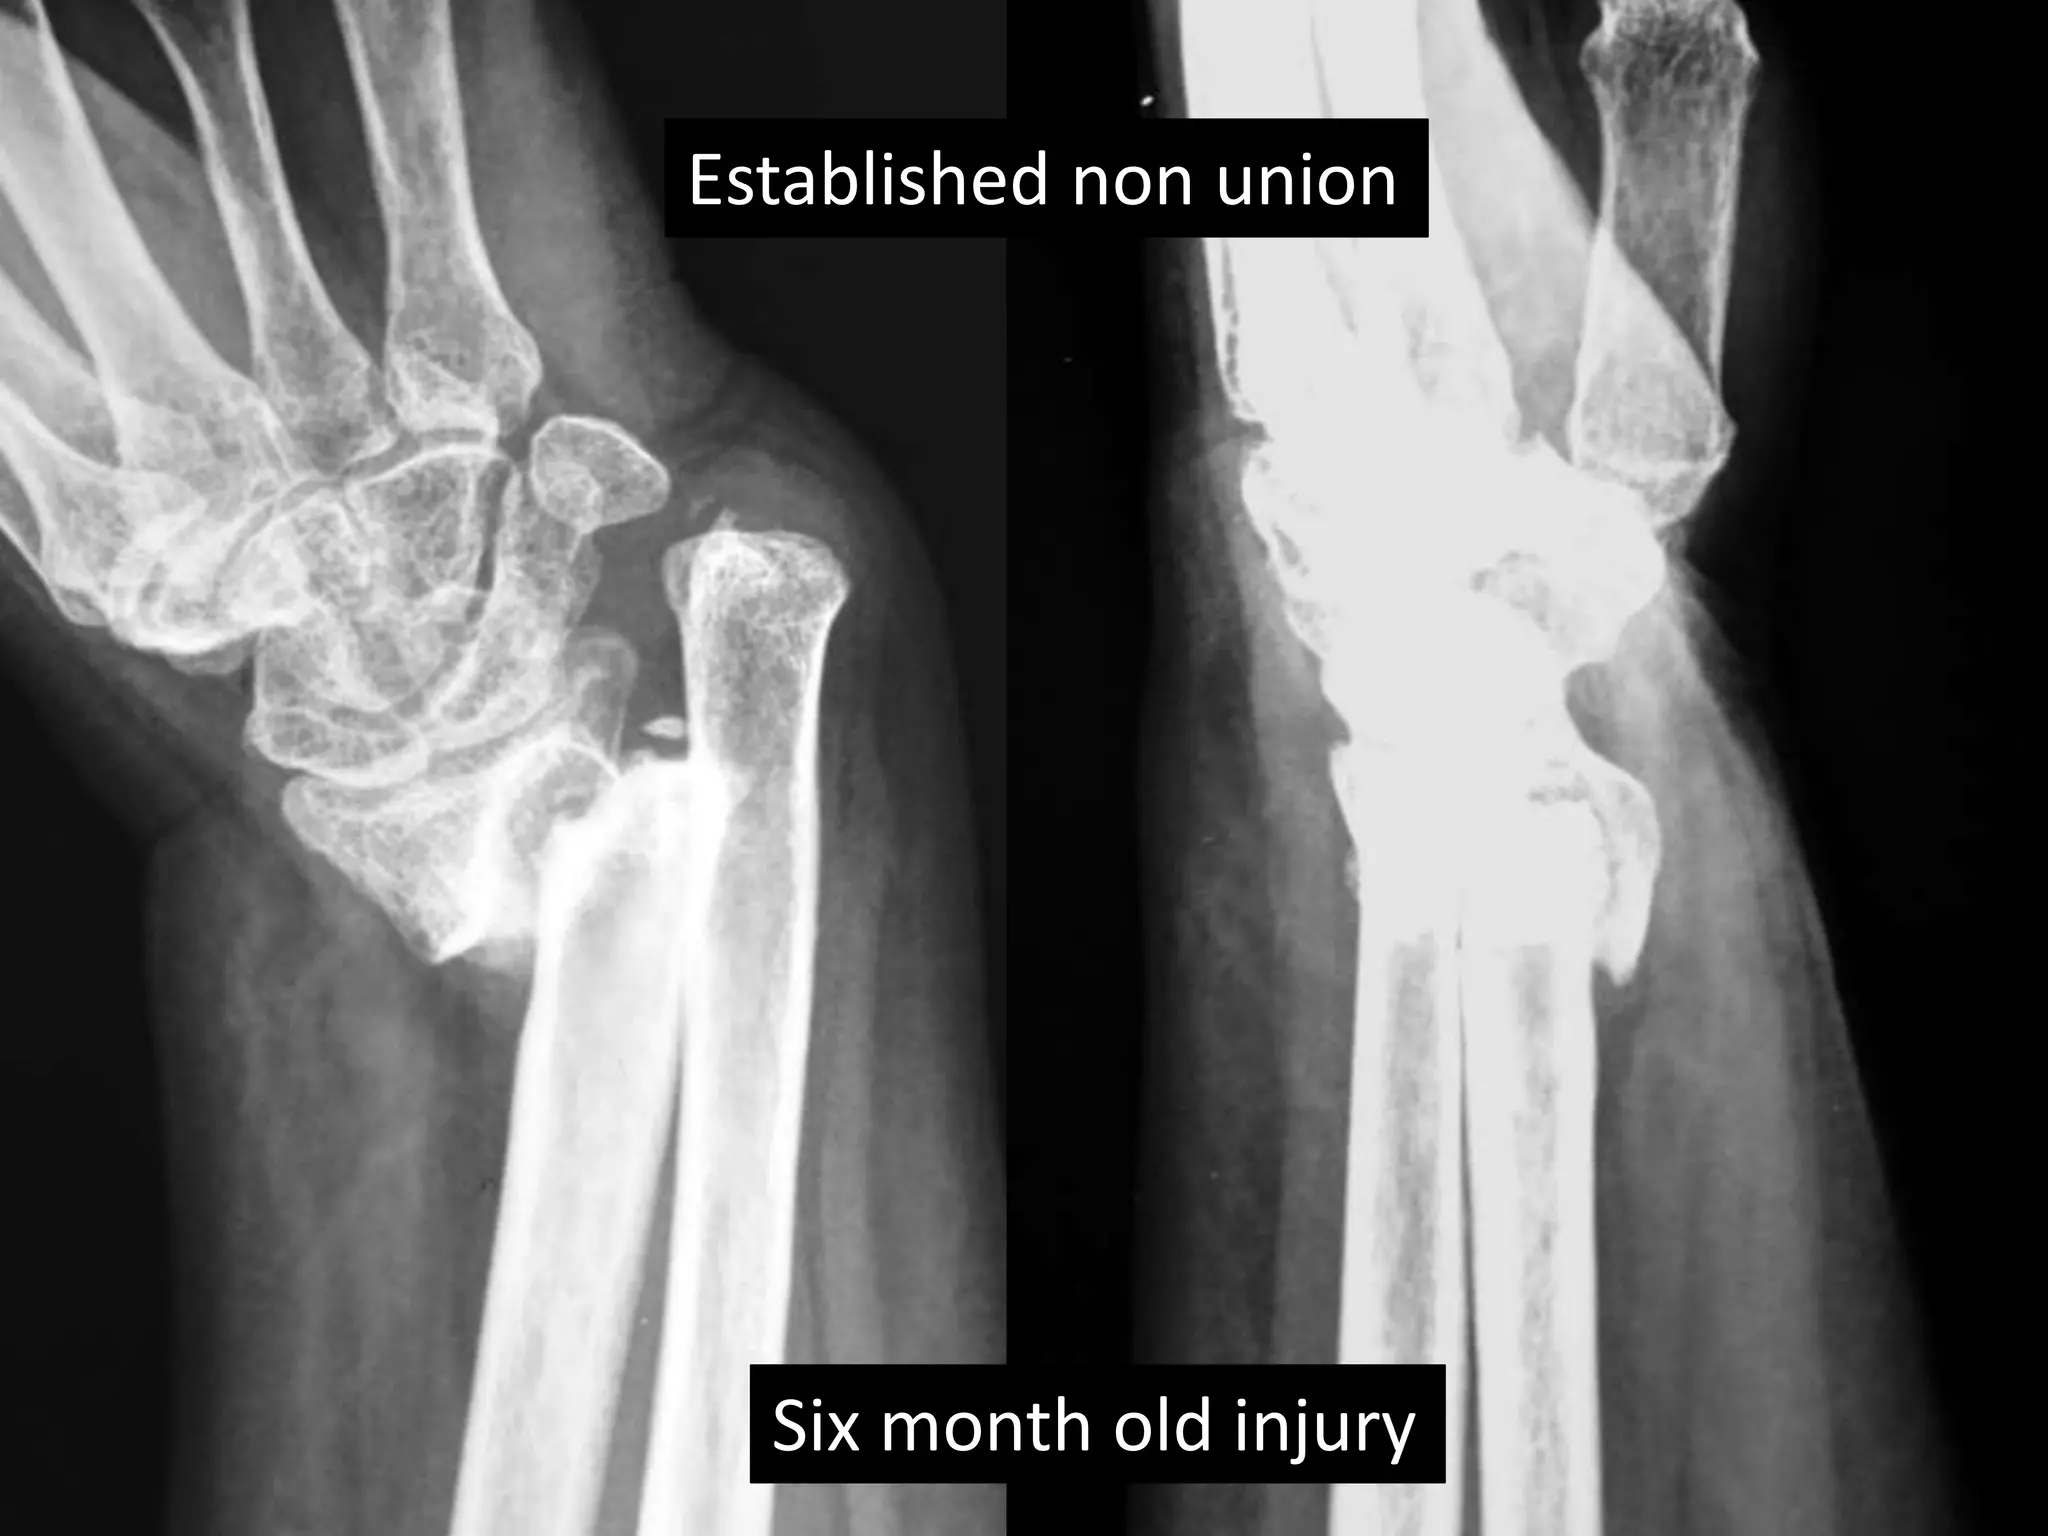

Case two

• 50 years old female

• Low energy injury

• Sustained fracture lower end radius

• Pop cast for six weeks

• Progressively increasing deformity following

removal of plaster.

• X- rays after six months following fracture

showing non-union.

Established non union

Six month old injury

Surgery

• Volar exposure

• Removal of scar tissue and clearing of bone

ends.

• Release of soft tissue contractures.

• Shortening of ulna and plating.

• Plating of radius with bone grafting.

Case two •50 years old female • Low energy injury • Sustained fracture lower end radius • Pop cast for six weeks • Progressively increasing deformity following removal of plaster. • X- rays after six months following fracture showing non-union.

• 40.

Established non union Six month old injury

Surgery • Volarexposure • Removal of scar tissue and clearing of bone ends. • Release of soft tissue contractures. • Shortening of ulna and plating. • Plating of radius with bone grafting.